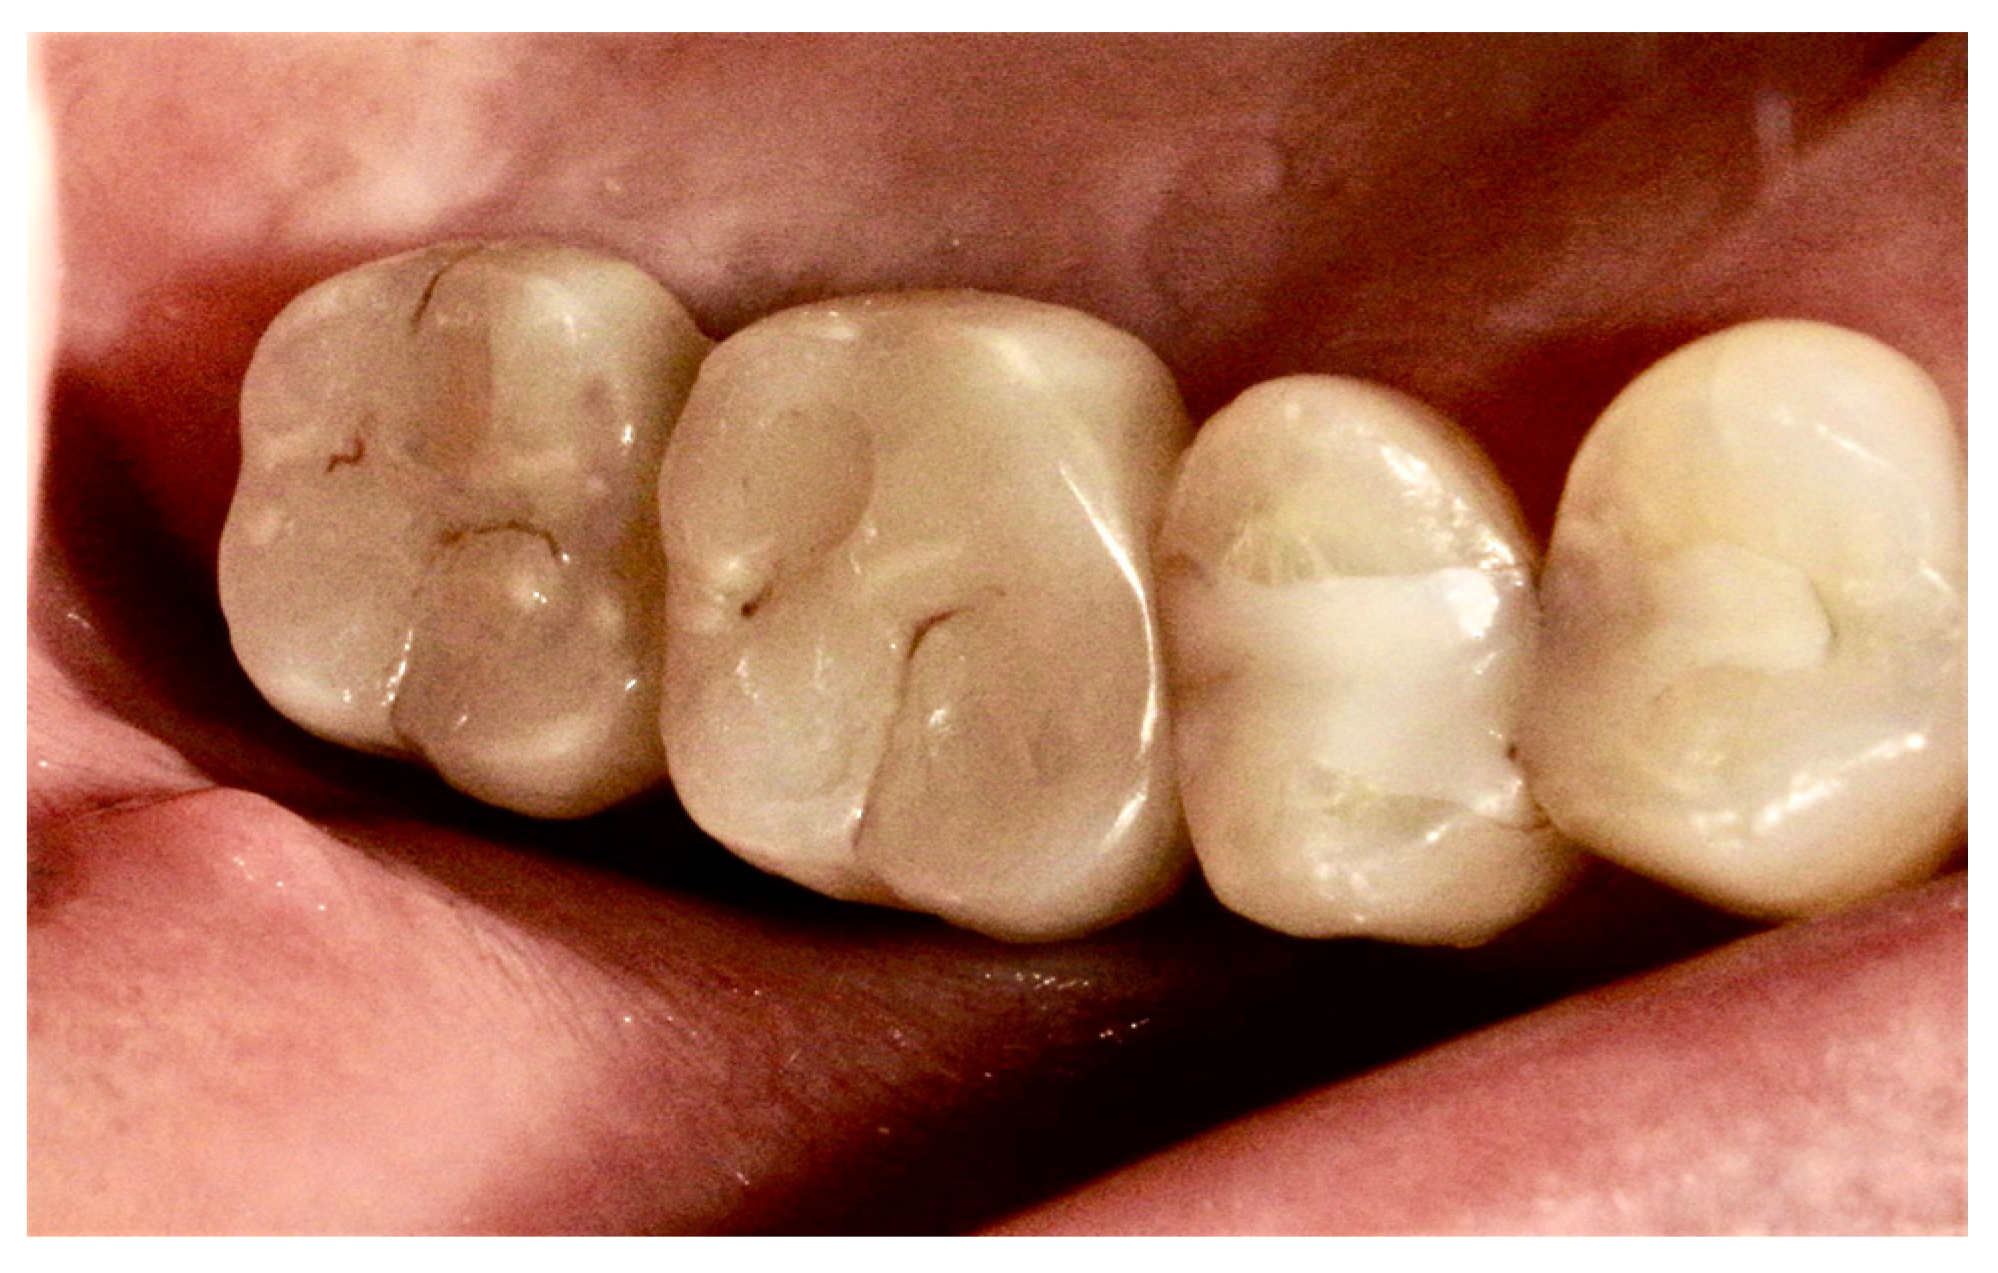

The final diagnosis of idiopathic osteosclerosis was confirmed. A six-month follow-up showed good healing, and prosthesis on dental implants was performed (Figure 8, Figure 9 and Figure 10).

Figure 8.

Good healing of soft tissues.

Figure 10.

Crowns on implants.